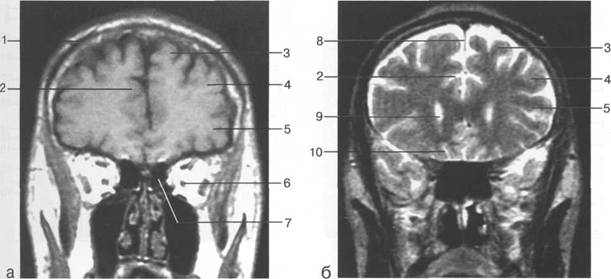

Задняя череп 13513u2010n 85;ая ямка представляет собой часть основания череп 13513u2010n 72;, ограниченную централь

Следует отметить, что в настоящее время оптимальным методом исследования структур задней череп 13513u2010n 85;ой ямки является МРТ, которая, в отличие от КТ, лишена артефактов от кост

Мозжечок заполняет практически весь объем задней череп 13513u2010n 85;ой ямки. Его поперечный раз

височная доля; 17 - полушарие мозжечка; 18 - |

Следует остановиться на анатомии подпаутинных пространств задней череп 13513u2010n 85;ой ямки IV 20 мм. Между основанием череп 13513u2010n 72; и нижней поверхностью мозга от большого затылочного отверстия вдоль ската и спинки турецкого седла простирается задняя базальная цистерна. В зави IV